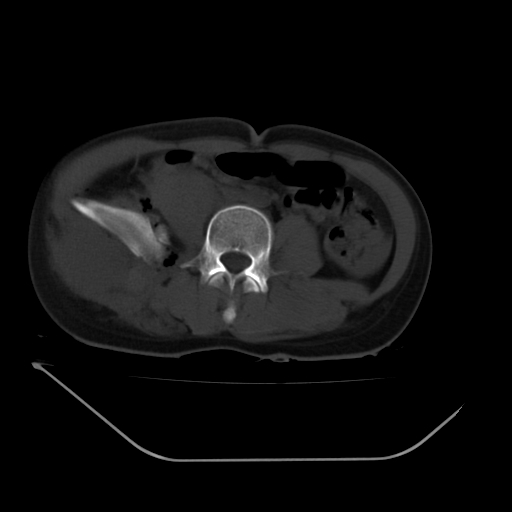

以下是引用liuyue在2008-7-19 13:02:00的发言:[br]1.肝右叶后下段及右肾挫裂伤伴腹腔积血。[br]2.右侧多发性肋骨骨折、横突骨折、右髂骨骨折伴周围软组织挫伤。[br]3.右侧腰大肌肿胀,并可见低密度影,如为气体,则肠道挫裂伤待除外。

以下是引用zhengfaming在2008-7-19 14:42:00的发言:[br]1.肝右叶后下段及右肾挫裂伤伴腹腔积血。脾脏挫裂伤待排[br]2.右侧多发性肋骨骨折、横突骨折、右髂骨骨折伴周围软组织挫伤。[br]3.右侧腰大肌肿胀,并可见低密度影,如为气体,则肠道挫裂伤待除外

以下是引用道哥在2008-7-19 16:52:00的发言:[br]肝右叶后下段及右肾挫裂伤、脾破裂伴腹腔积血。[br]2.双侧多发性肋骨骨折、横突骨折、右髂骨骨折伴周围软组织挫伤。[br]3.右侧腰大肌肿胀,并可见低密度影,如为气体,则肠道挫裂伤待除外。